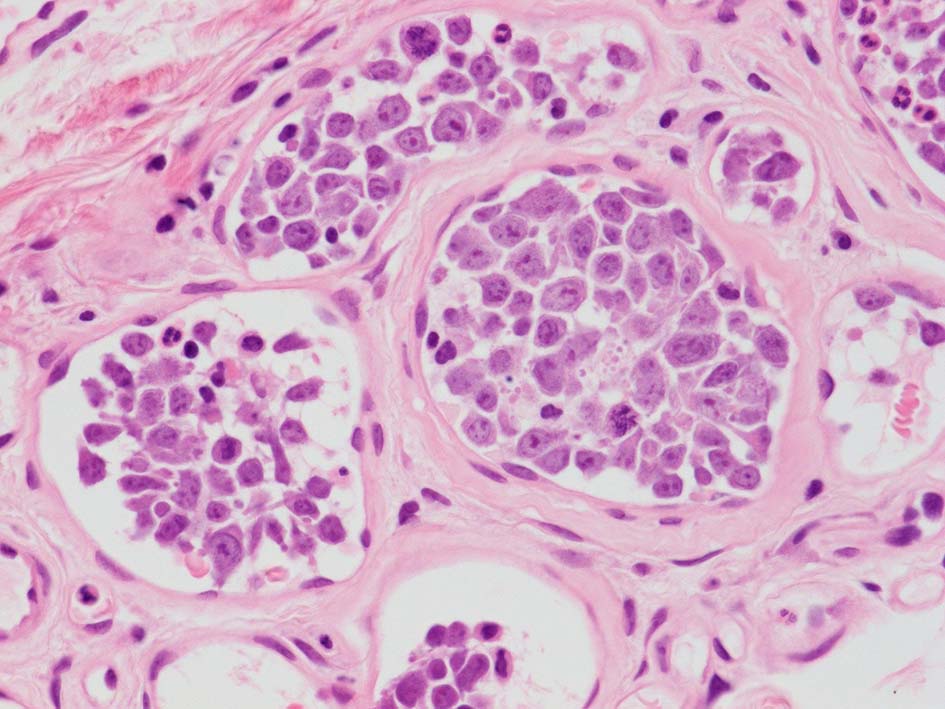

腎臓;糸球体係蹄内に腫瘍細胞が増殖するほか細腎動脈にもみとめられる。

生検組織により血管内腔を塞ぐように大型異型リンパ球が増殖していることを確認することが診断の要件である。血管内増殖の病変分布が本病型では, 脳, 肺, 肝, 腎, 副腎, 皮膚, 骨髄など特有である。しかし大細胞型B細胞リンパ腫にはこのような臓器を選択的に侵襲するが, 血管内腔には増殖しないものがあることに留意が必要である。